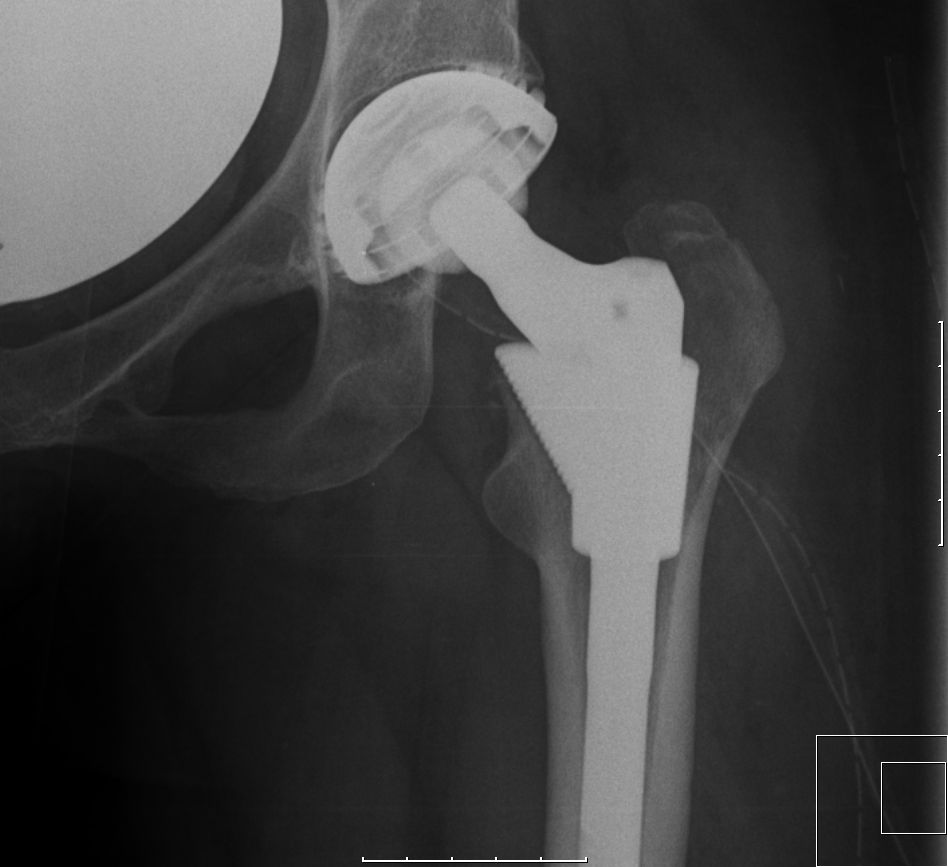

| Resektion des Femurkopfes und des Schenkelhalses. TEP. | ![]() | |